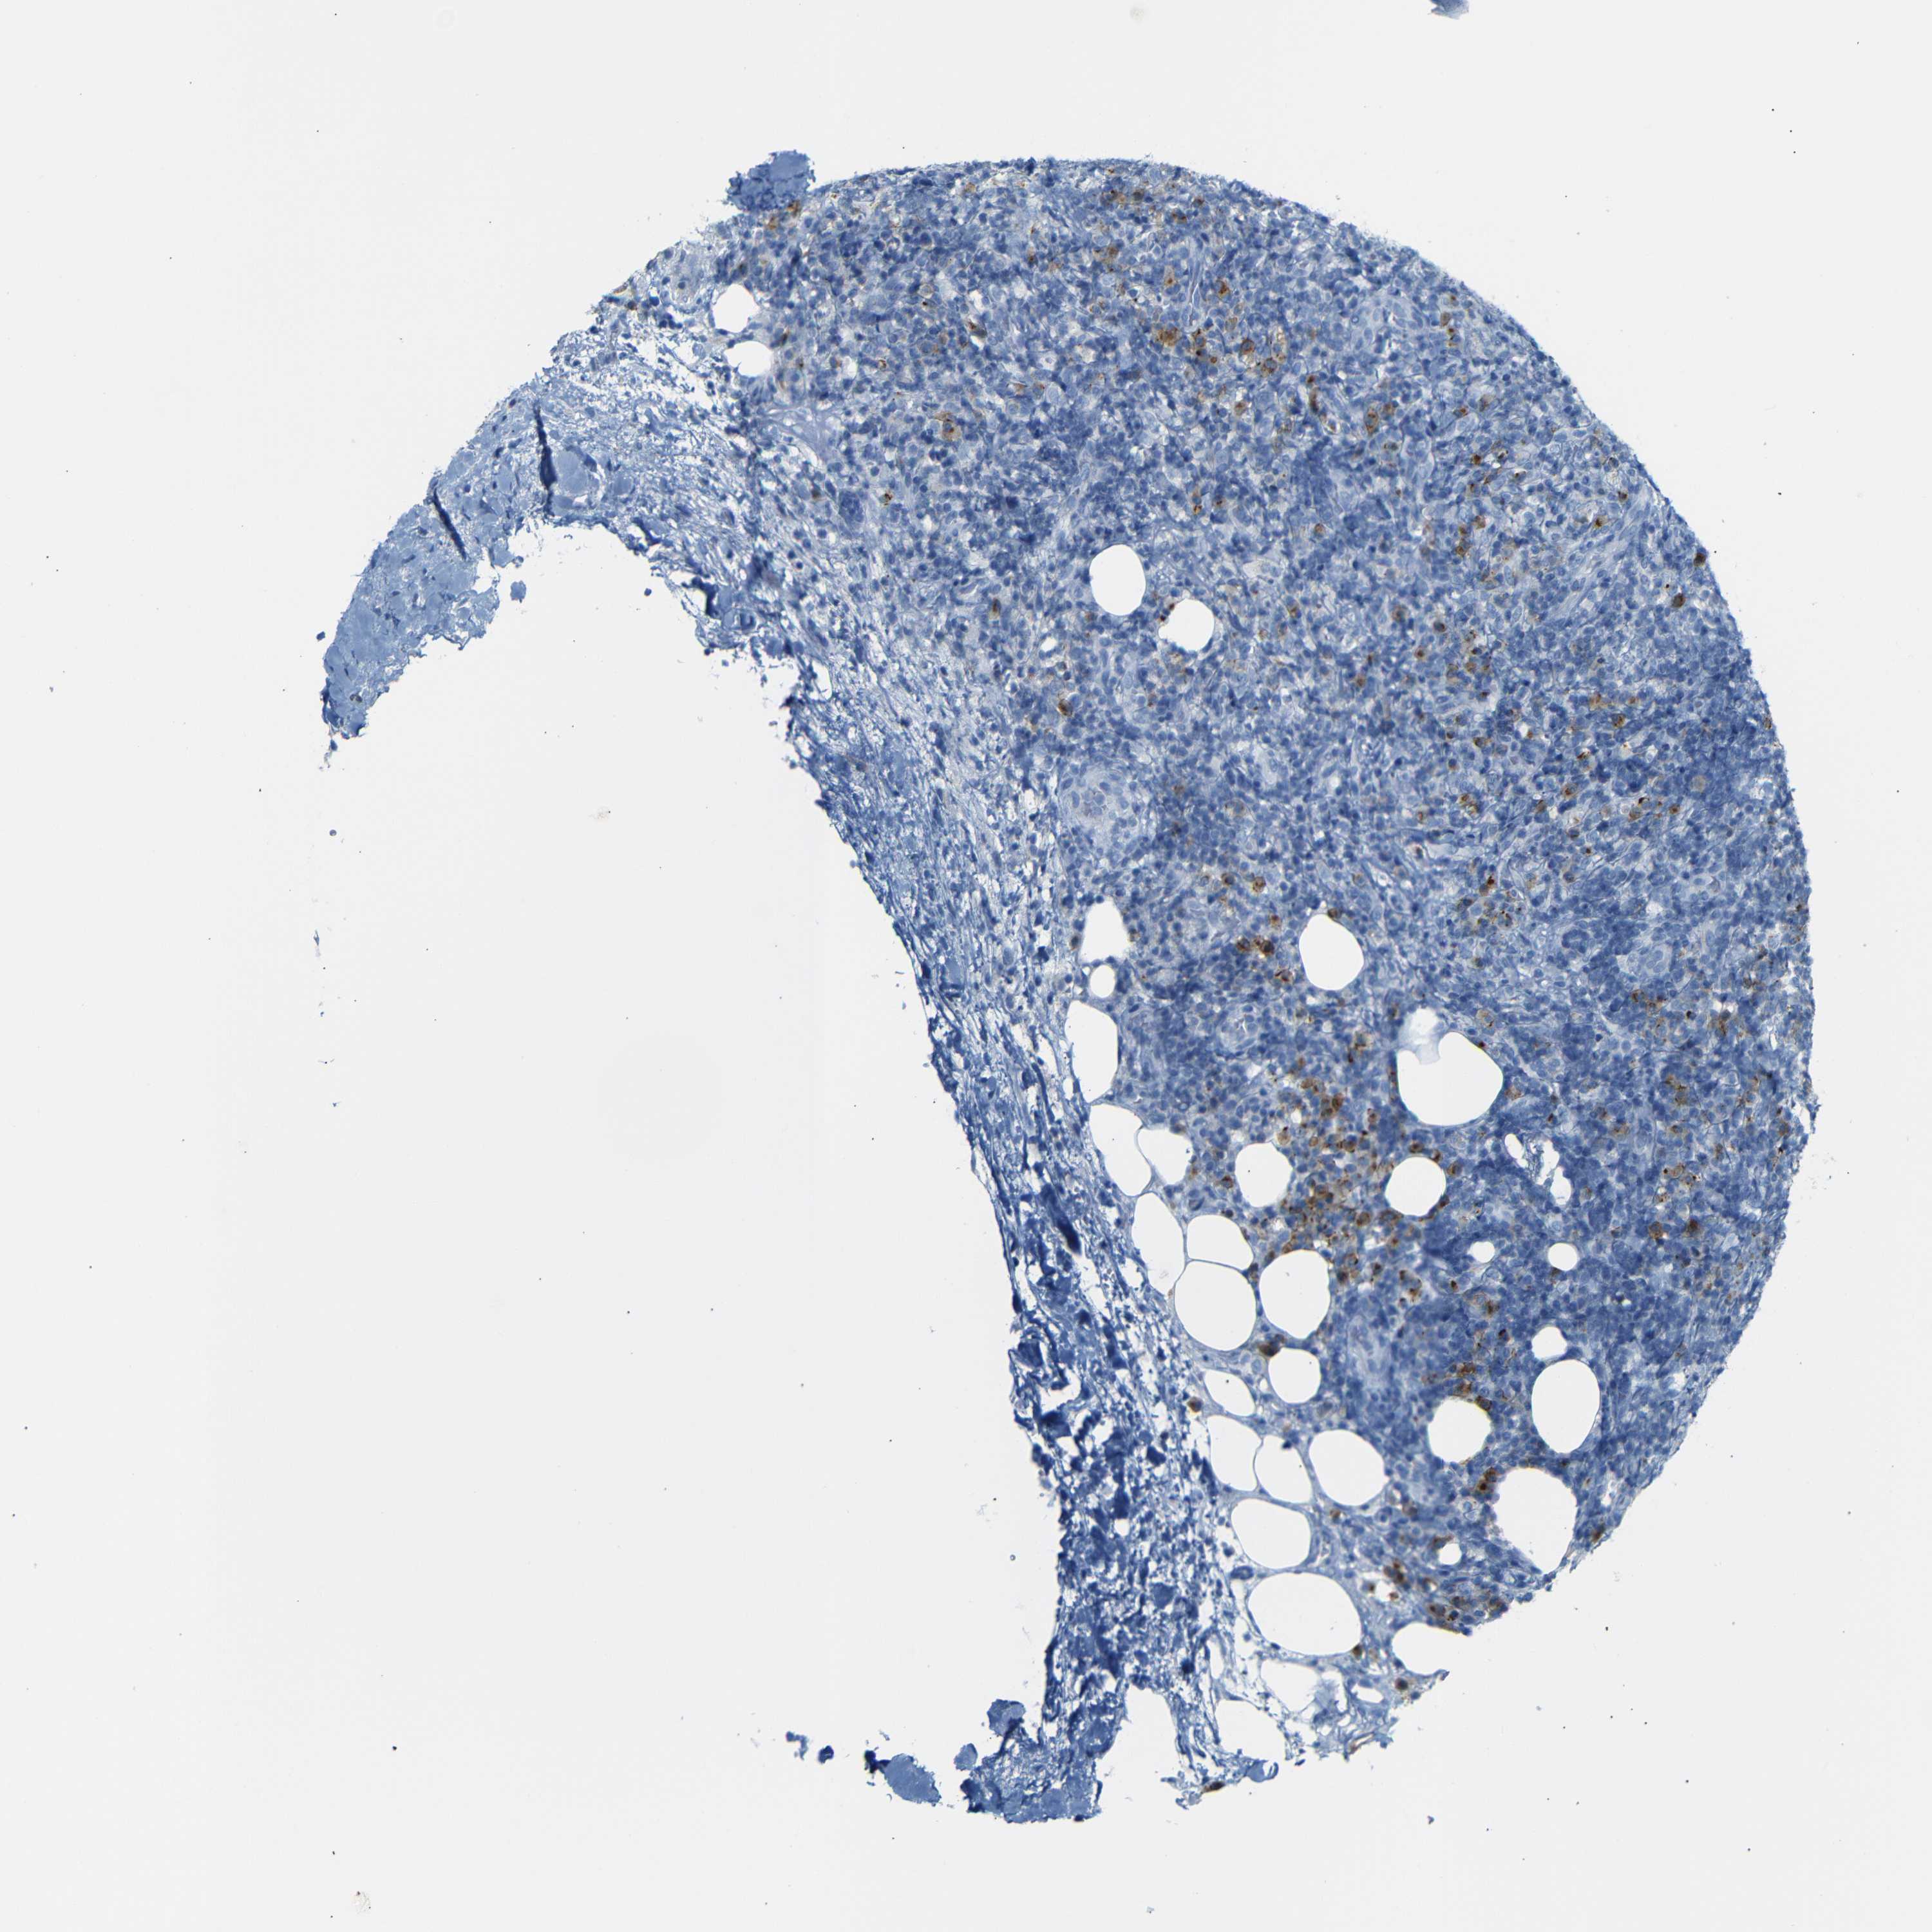

LYMPHOMA - Protein expressioni

A mouse-over function shows sample information and annotation data. Click on an image to view it in a full screen mode. Samples can be filtered based on level of antibody staining by selecting one or several of the following categories: high, medium, low and not detected. The assay and annotation is described here.

Antibody stainingi

Antibody staining in the annotated cell types in the current human tissue is reported as not detected, low, medium, or high, based on conventional immunohistochemistry profiling in selected tissues. This score is based on the combination of the staining intensity and fraction of stained cells.

Each image is clickable and will lead to virtual microscopy that enables deeper exploration of all samples and also displays staining intensity scores, fraction scores and subcellular localization as well as patient and tissue information for each sample.

Antibody HPA013323

Hodgkin's disease, NOS

Malignant lymphoma, non-Hodgkin's type, High grade

Malignant lymphoma, non-Hodgkin's type, Low grade